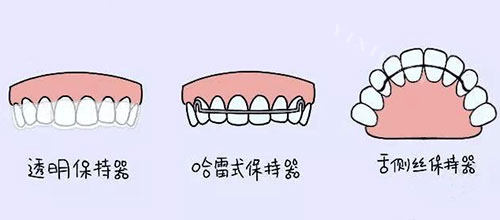

MBT 托槽矫正的价格大约在 8000 - 12000 元,Roth 托槽矫正的价格约为 10000 - 15000 元,而定期复诊与保持器费用约为 1000 - 3000 元。当然,具体的价格还会受到地区、医院、医生技术水平等多种因素的影响。

MBT 托槽和 Roth 托槽各有其独特的优势和适用范围。MBT 托槽适合那些对美观性和舒适度有较高要求的患者,而 Roth 托槽则更适合需要进行复杂矫正,尤其是拔牙矫正的患者。在选择托槽时,患者需要充分考虑自身的具体情况、舒适度要求以及美观性等多方面因素。